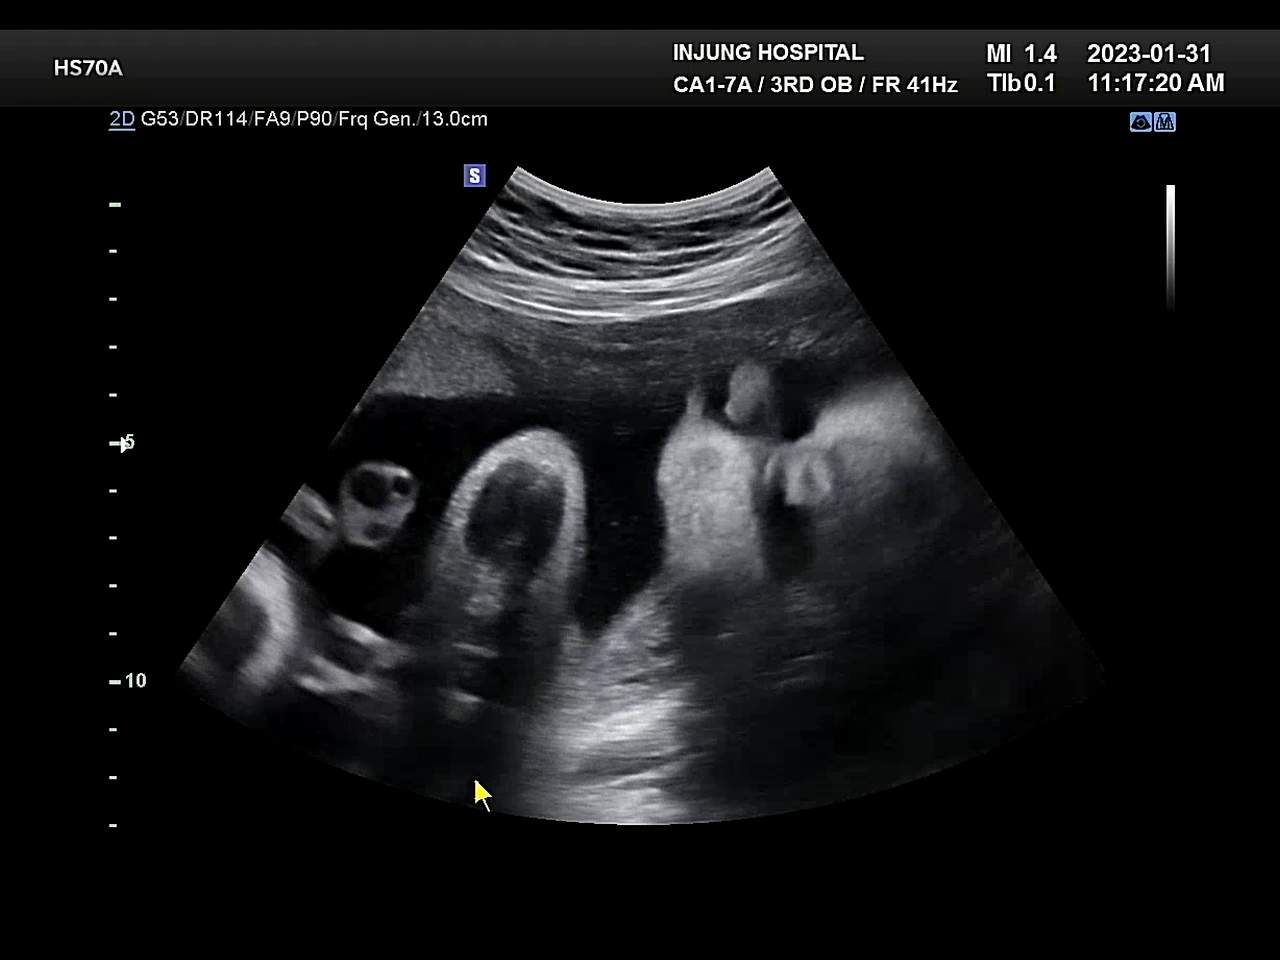

도리도리하는 포도

31주 진료는 무난했다. 이제 큰 검사들도 다 끝나서, 초음파로 아이의 상태를 체크하는 정도로 진료가 끝난다. 담당선생님은 별다른 이상이 없어도 초음파를 자세히 봐주시는 편인데, 덕분에 포도가 도리도리 하는 모습을 봤다. 어찌나 신기하고 귀엽던지. 요즘은 자꾸 포도를 보고 싶다는 말을 하게 된다. 포도야 얼른 쑥쑥 자라렴!